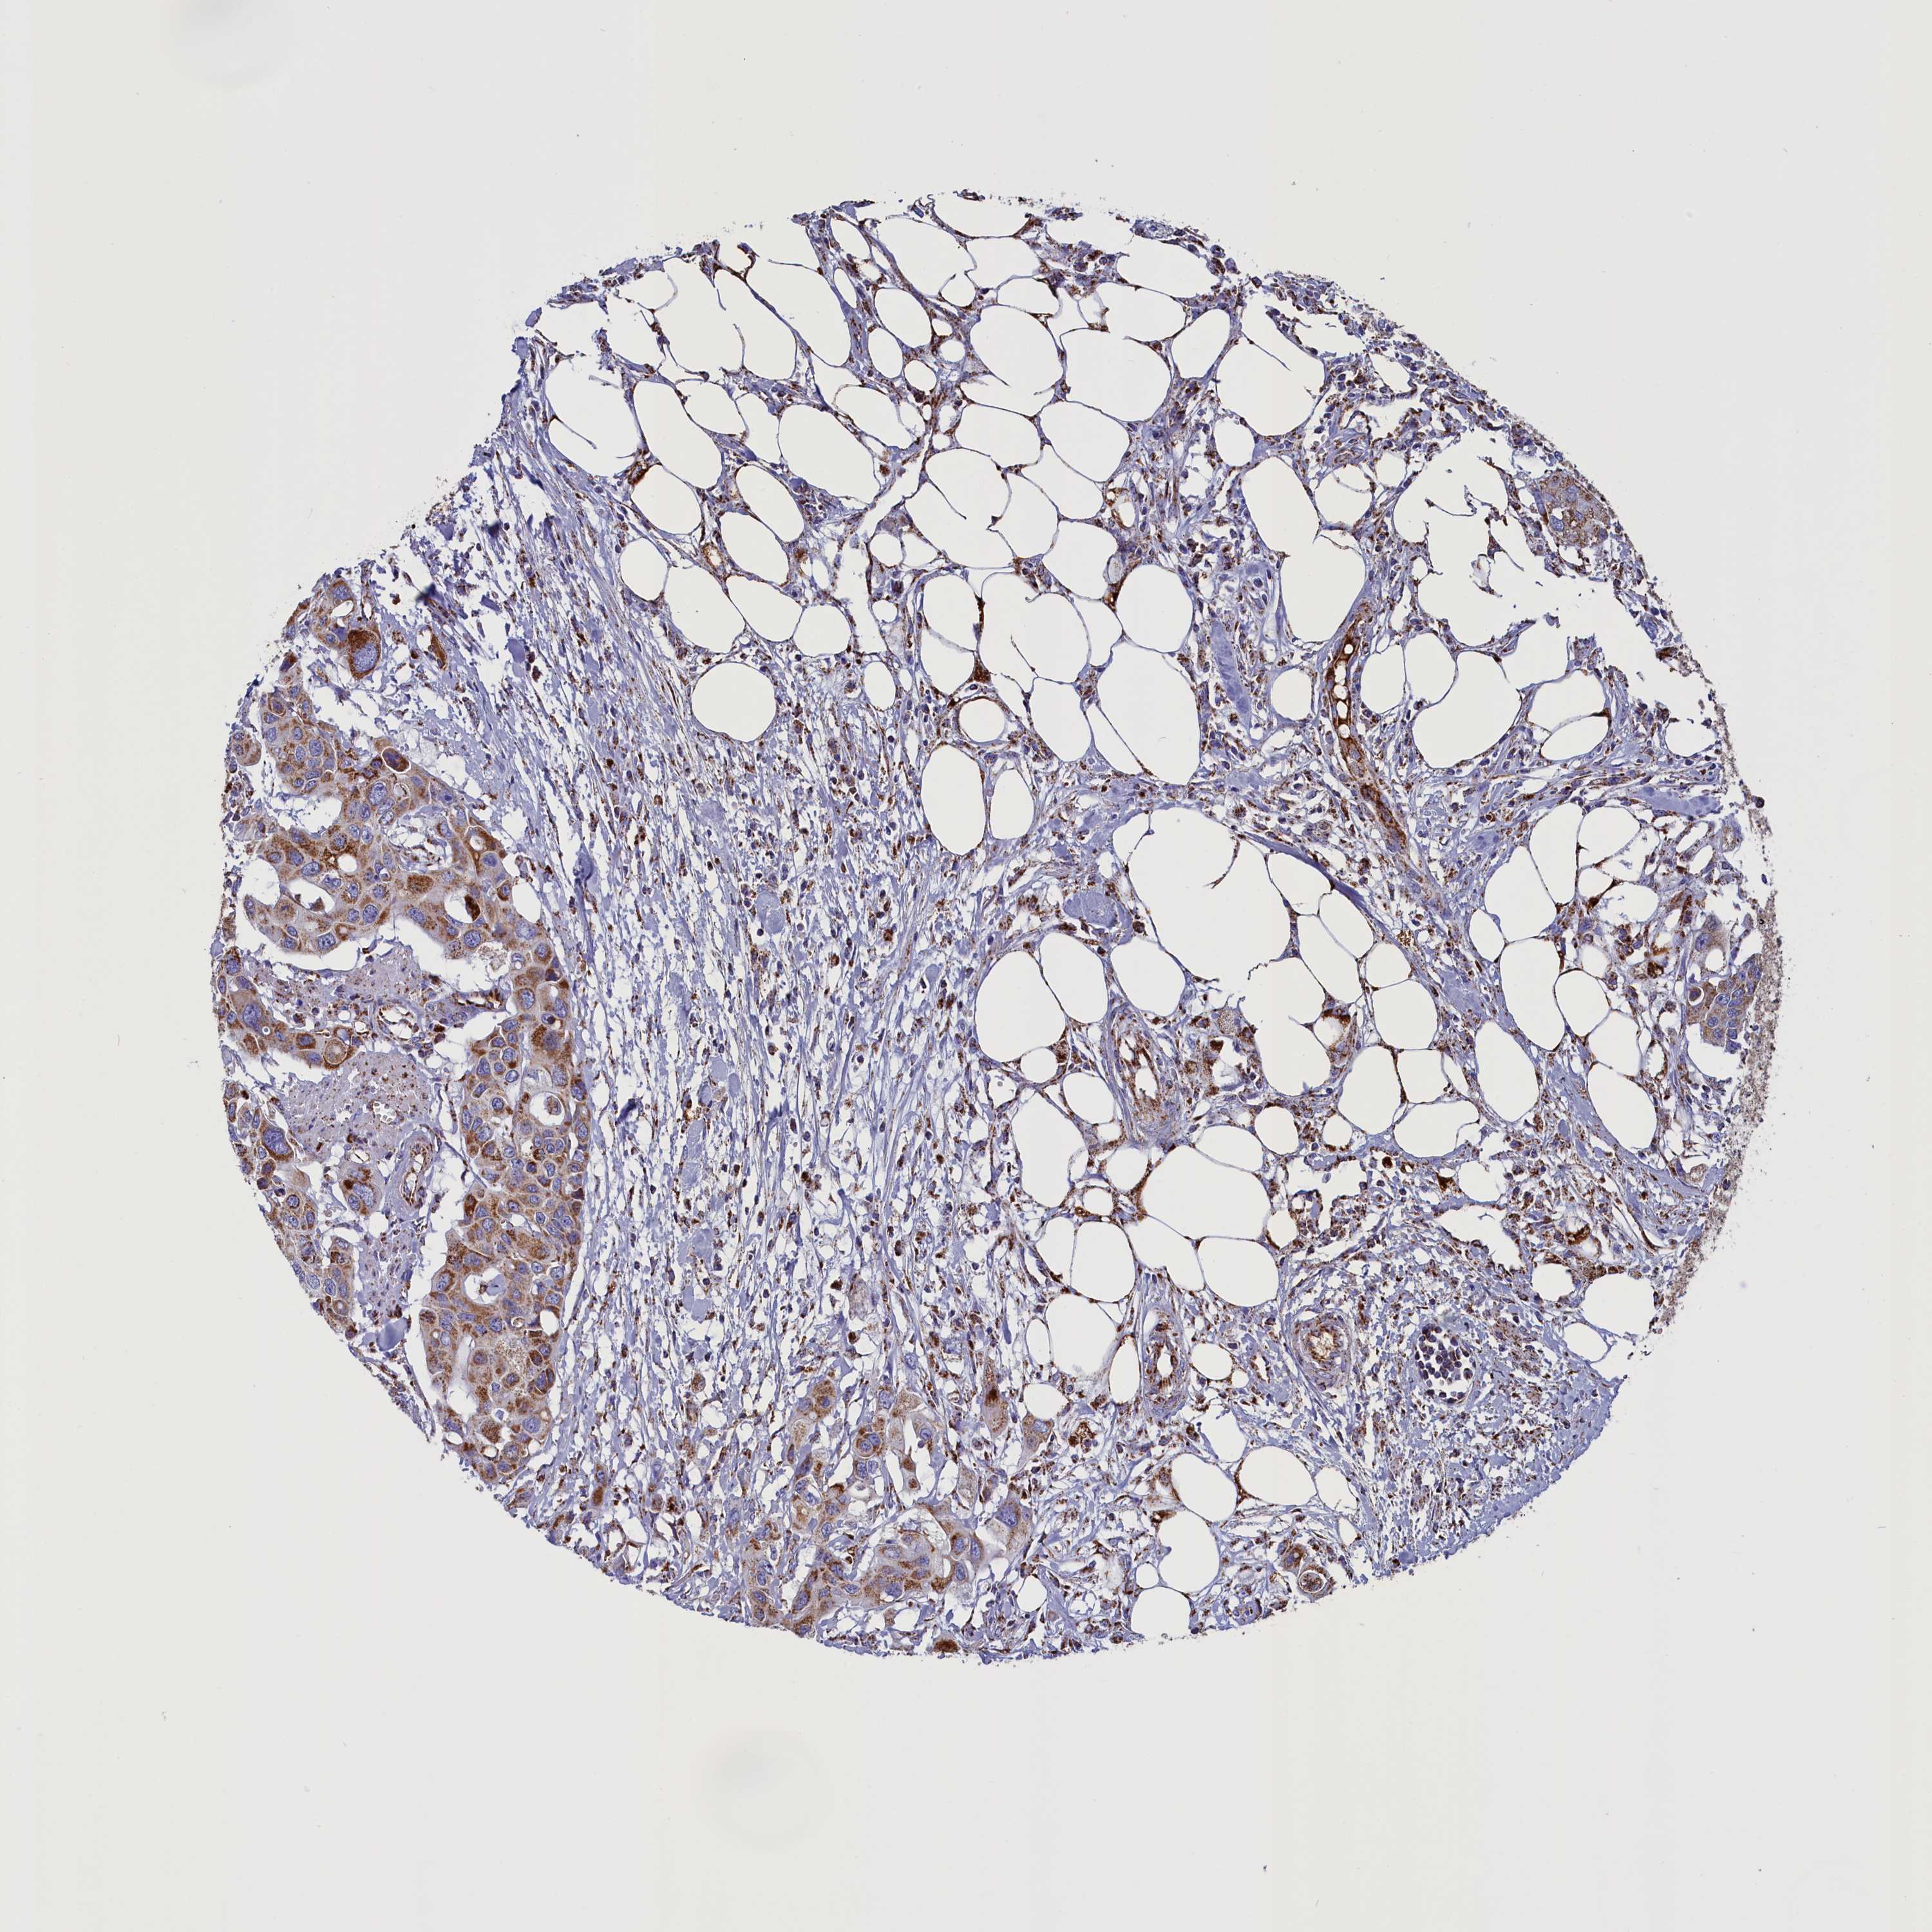

CANCER COLORECTAL CANCER Show tissue menu

Colorectal cancer

Human cancer

Colon adenocarcinoma

Rectum adenocarcinoma